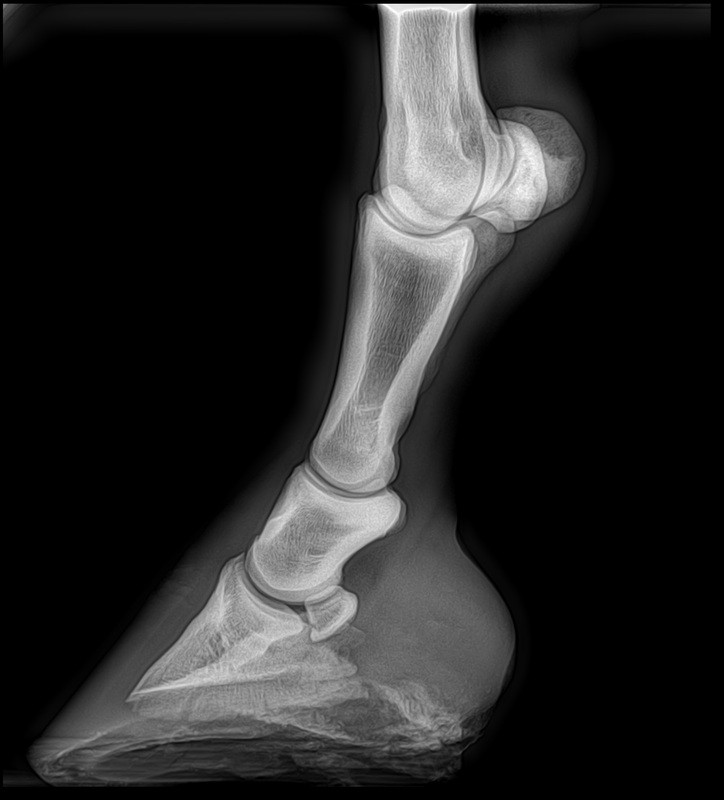

From www.merckvetmanual.com

From www.msdvetmanual.com